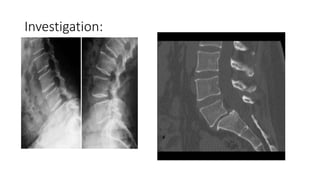

Investigation: